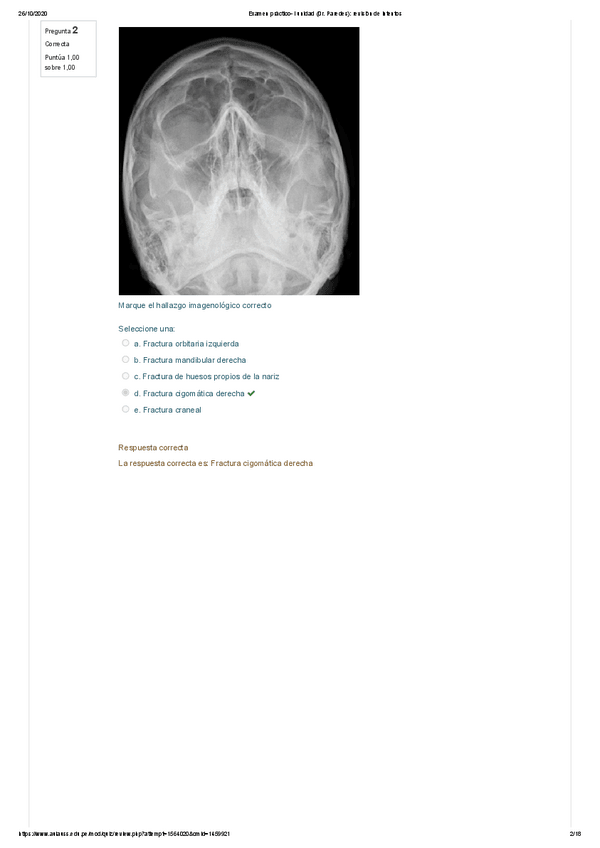

Examen práctico Primer Parcial

18 páginas